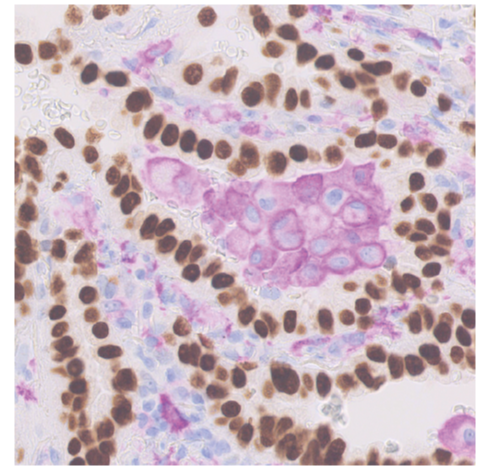

そこで次に、肺胞マクロファージの RNA 配列を読み取って、遺伝子発現を網羅的に定量する「RNA シークエンス」を行いました。その結果、肺胞マクロファージは肺がん組織ではアクチビン A というタンパク質を産生し、これが肺がんの増殖を促進していること、アクチビン A を抑制することにより、肺がんの増殖が緩やかになることを解明しました。さらに、ヒトの肺がん組織でも解析を行い、特に早期がんの場合において、肺胞マクロファージがアクチビン A を発現していることが確認されました。

また、この研究で解明された肺胞マクロファージのメカニズムは、早期の肺がんの段階から確認されており、肺胞マクロファージとアクチビンAに着目することで、肺がんを早期に診断することにも貢献できると考えられます。さらに、アクチビンAの阻害は、早期がんから進行がんへの進展を抑えることにも有用であると考えられ、肺がんを早期の段階で手術により根治する機会を増やすことにも貢献できると期待されます。